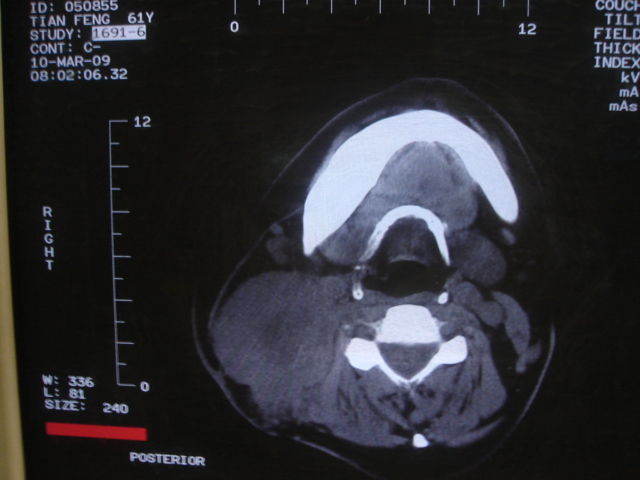

患者 男 61  甲状腺ca术后7年 颈部淋巴结转移

声门下区表面不光整,增厚呈局限性突起,未见局部浸润.

考虑----颈部淋巴结转移,不排除---喉乳头状瘤可能.

颈部多个淋巴结增大,结合甲状腺ca术后7年病史考虑转移。

另声门区不规则突起,建议喉镜检查!

右侧颈部淋巴结转移,右声带乳头突起,乳头状瘤可能性大。

1)右侧颈部淋巴结转移瘤。2)右侧声带新生物,性质待定;建议喉镜检查(活检)。

结合病史符合甲状腺ca术后颈部淋巴结转移